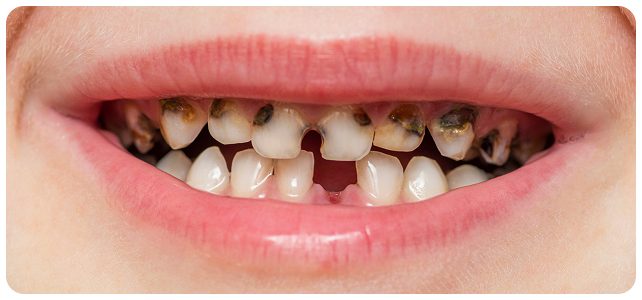

At around 6 years old, children prepare to lose their first tooth, and primary (baby) teeth will gradually be replaced by permanent teeth. The tooth replacement sequence typically begins with the eruption of the first molar (tooth number 6) and ends with the eruption of tooth number 7 around the age of 12.

During this stage, parents should closely monitor their child’s tooth replacement process and schedule regular dental check-ups. This helps detect common abnormalities early, such as missing tooth buds, extra teeth in the midline gap, or impacted teeth (mesiodens), which can obstruct tooth eruption and affect the positioning of the remaining teeth.